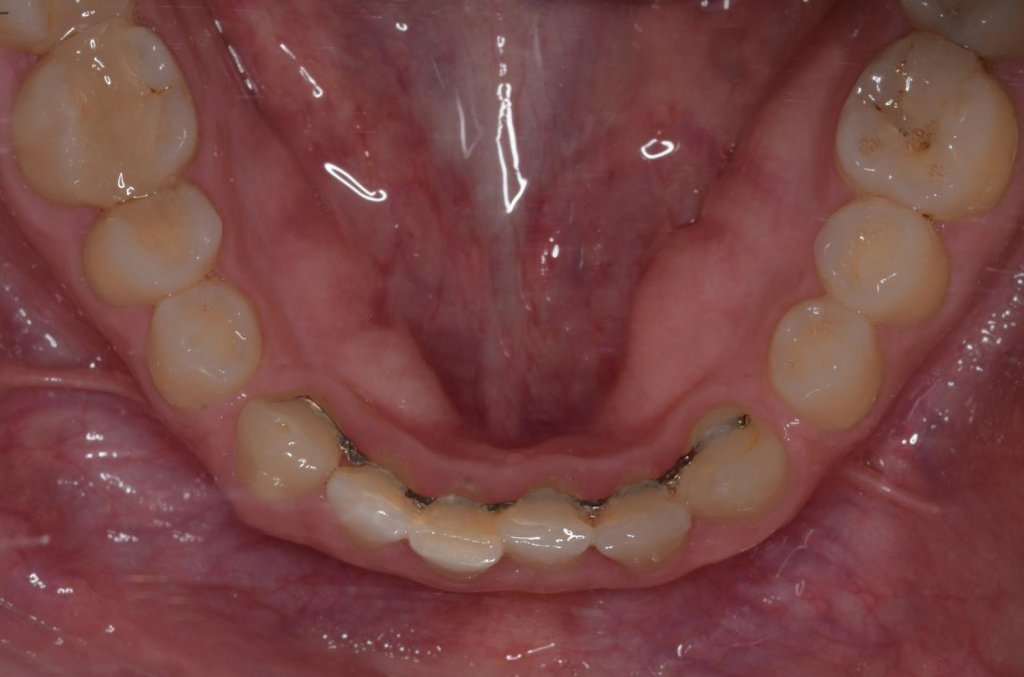

Tras 12 meses de ortodoncia, llevada a cabo por mi colega la Dra. Celia Pisonero (un bravo por ella), conseguimos nuestro objetivo:

Esto es el resultado después de la ortodoncia, no os dejéis engañar por la gingivitis de los inferiores, es tras la retirada.